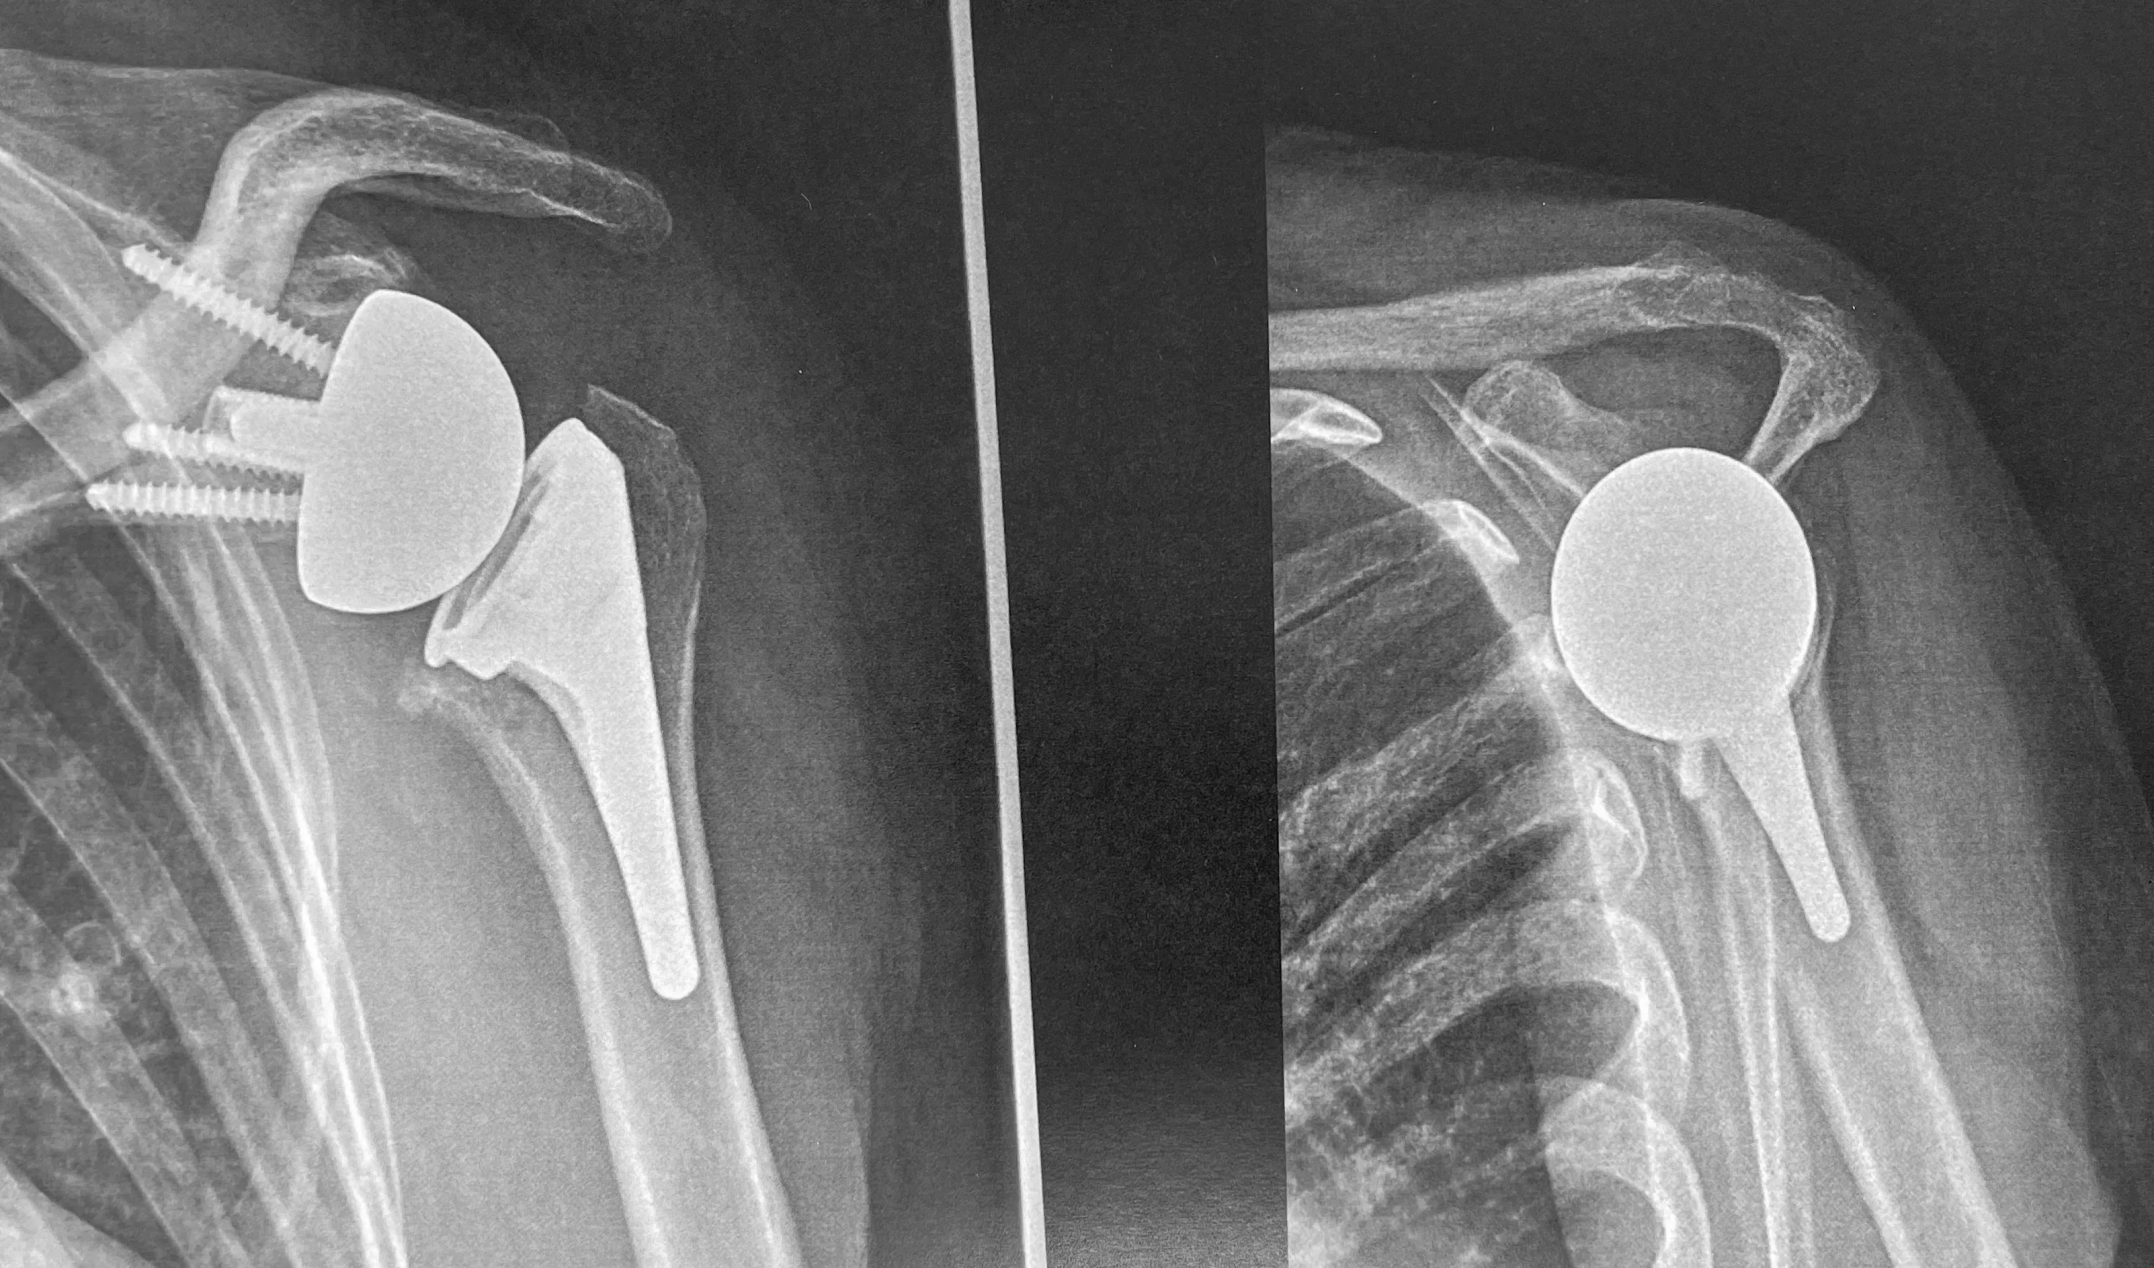

Dans un premier temps des radiographies permettent d'avoir une orientation diagnostic en corrélation avec l'examen clinique du chirurgien. Il s’agit du bilan de débrouillage qui sera complété le plus souvent par un arthro-scanner (plus rarement une IRM).

Si votre médecin généraliste vous oriente vers le chirurgien il pourra, afin de vous faire gagner du temps, vous prescrire ces examens complémentaires (radiographies + arthroscanner). Ceux-ci seront indispensables pour définir précisemment les gestes de réparation qui seront nécessaires au traitement.

Aspect radiographique d'une omarthrose primitive